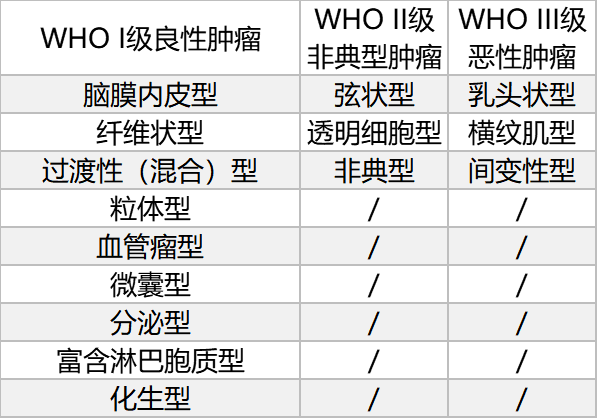

世界卫生组织(WHO)分类方案根据显微镜下的细胞类型将脑膜瘤分成15种组织亚型。这些组织学亚型分为三个等级(WHO I-III级),组织分型通常根据细胞学特征反映肿瘤生长速率和复发的可能性。非典型脑膜瘤(WHO II级,占脑膜瘤病例的18%)表现出组织和细胞异常增加。这些肿瘤的生长速度快于良性脑膜瘤,通常以脑部侵袭为特征。非典型脑膜瘤比良性脑膜瘤(WHO I级)复发的可能性更高。恶性脑膜瘤(WHO III级)显示细胞异常增加,并且比良性和非典型脑膜瘤的生长速度更快。恶性脑膜瘤比其他两种亚型更容易侵袭大脑并且复发频率更高。

来源于世界卫生中枢神经系统肿瘤WHO分类